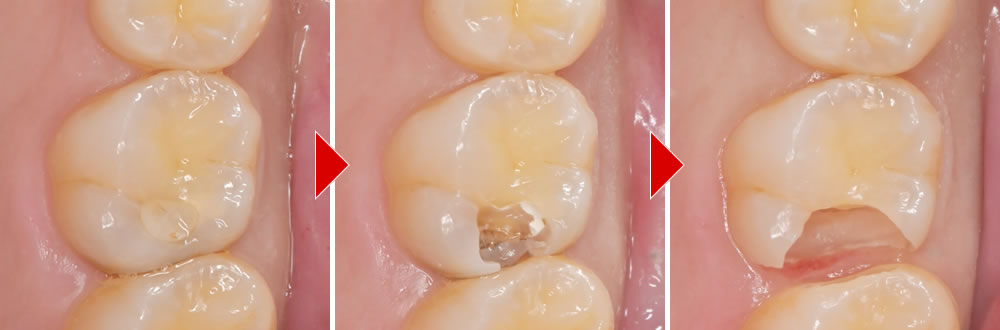

治療前の口腔内写真とレントゲンです。左上第一大臼歯に大きな虫歯が認められます。

今回はBioMTAセメントという材料を使用し、歯の神経を温存する治療を行っていきます。

虫歯の除去

う蝕検知液を用いて、虫歯部分を丁寧に除去しました。